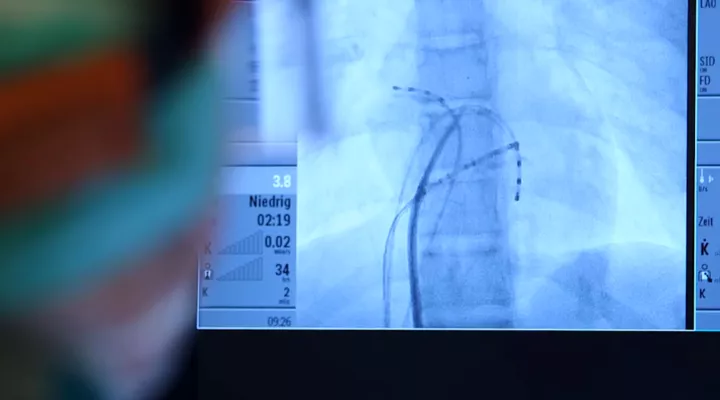

Minimal-invasive Diagnostik und Behandlung im Herzkatheterlabor

In unserem spezialisierten pädiatrischen Herzkatheterlabor führen wir pro Jahr mit grösster Expertise und dem Einsatz optimaler und modernster Technologie ca. 350 minimal-invasive Eingriffe inklusive komplexer Interventionen und elektrophysiologischer Behandlungen (z. Bsp. Radiofrequenzablation) durch.

Diese Eingriffe (z. Bsp. Ballondilatationen oder Implantation von Verschluss-Schirmchen oder Stents) können sehr oft operative Verfahren vollständig ersetzen oder diese sinnvoll ergänzen. Teilweise finden auch Eingriffe gemeinsam und gleichzeitig mit der Herzchirurgin oder dem Herzchirurgen als sogenannte Hybrid-Verfahren statt. Das vollständig ausgestattete elektrophysiologische Katheterlabor - ausschliesslich für Kinder und Jugendliche - ist ein nationales Alleinstellungsmerkmal des Kinderspitals und ermöglicht dort eine entsprechende spezialisierte und effiziente Diagnostik und Behandlung in jeder Alterskategorie.

Herzkatheter

Bei diesem Eingriff kann der Kardiologe das Herz untersuchen und «reparieren», ohne zu operieren.